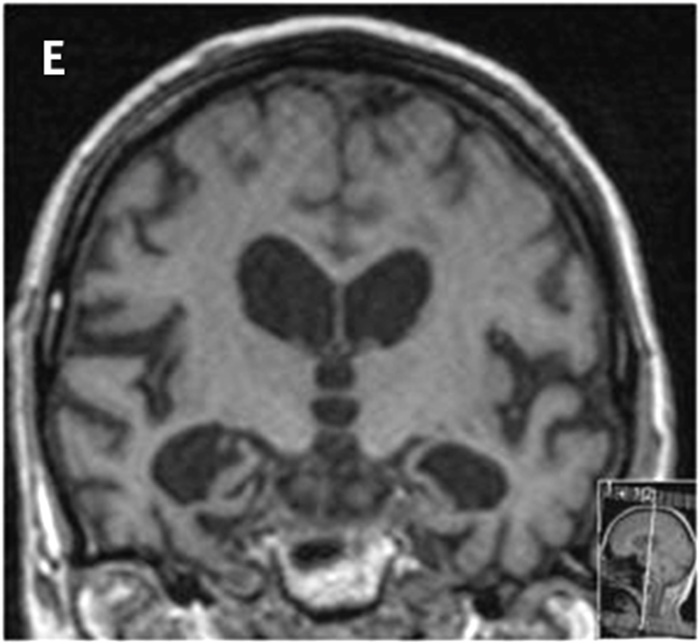

Bedömningen sker enligt en femgradig skala, 0–4, där MTA 0 och MTA 1 visar normala förhållanden och MTA 2–4 ökande grad av atrofi. MTA 2 är patologiskt hos patienter yngre än 70 år och MTA 3 är patologiskt hos alla patienter under 80 år, medan MTA 4 alltid måste uppfattas som patologiskt oavsett patientens ålder (Figur 1) [15].

Figur 1. MTA-graderna 0 (A), 1 (B), 2 (C), 3 (D) och 4 (E).